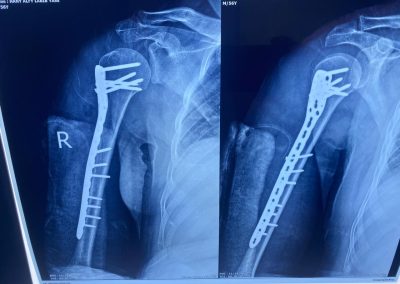

الاشعات بعد التثبيت تبين رجوع الكسر لطبيعته تمامًا.